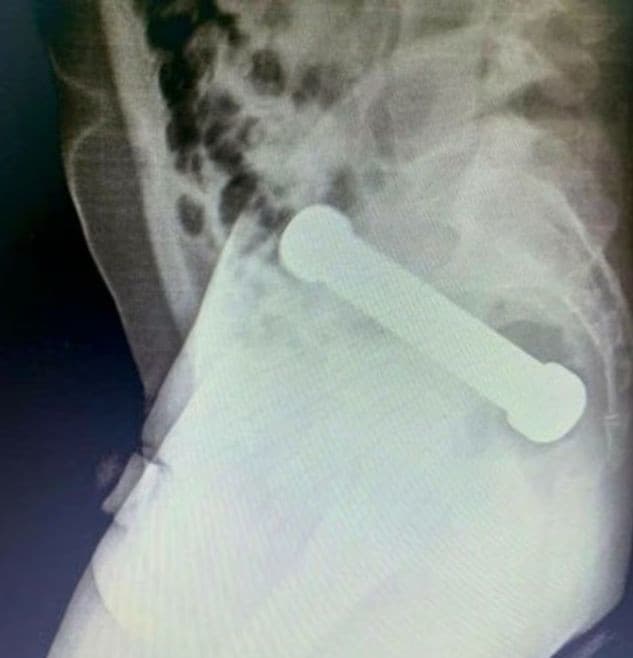

Zlom nastal až po röntgenovom vyšetrení. Lekári na snímke objavili kovovú činku dlhú približne 20 centimetrov s hmotnosťou okolo dvoch kilogramov, ktorá uviazla v oblasti konečníka a hrubého čreva.

Podľa dostupných informácií sa muž najprv pokúšal predmet odstrániť sám, no neúspešne. Až potom vyhľadal odbornú pomoc.